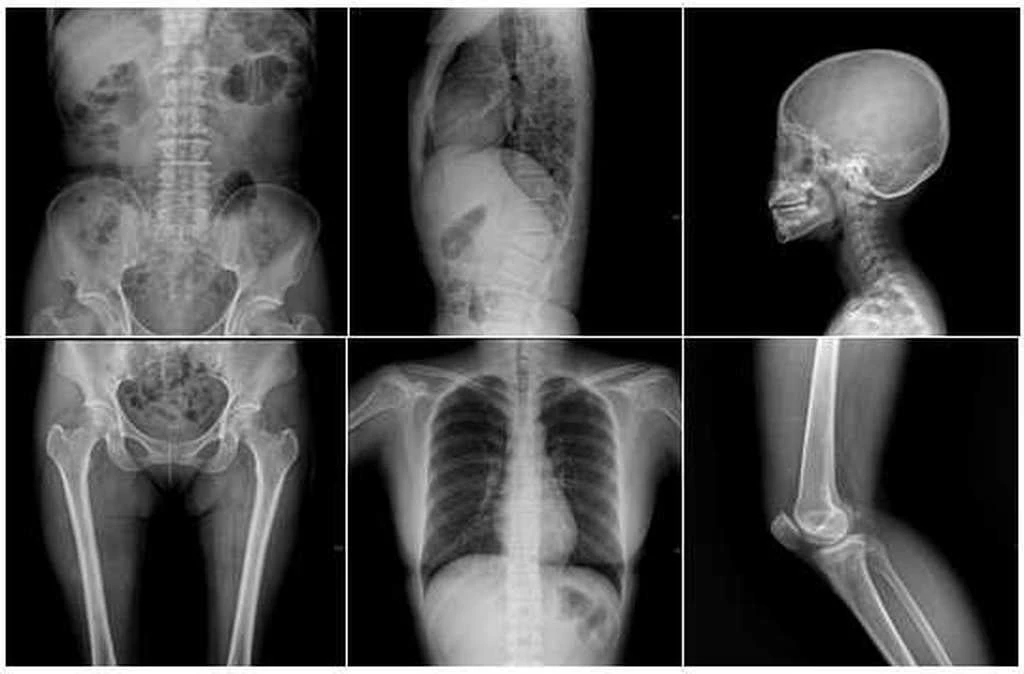

Ακτινογραφίες: Παχυσαρκία και καρκίνος άμεσα συνδεδεμένα – Περισσότερη ακτινοβολία για τα παχύσαρκα άτομα

Καρκίνος: Οι παχύσαρκοι που κάνουν ακτινογραφίες κινδυνεύουν περισσότερο

Οι πολύ παχύσαρκοι άνθρωποι χρειάζονται πολύ υψηλότερη δόση ακτινοβολίας κατά τις εξετάσεις ακτίνων-Χ, από ό,τι οι άνθρωποι κανονικού βάρους, με αποτέλεσμα να έχουν υπερδιπλάσιο κίνδυνο ...